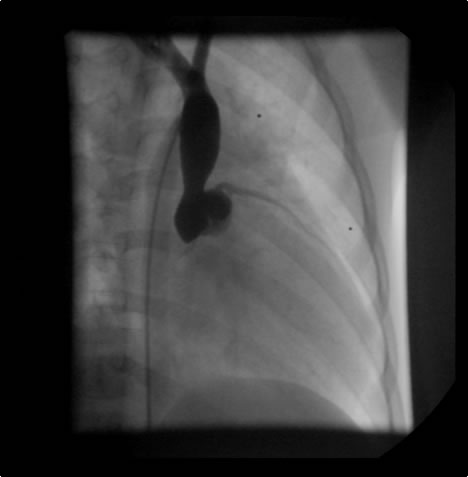

Diagnosis starts with a physical exam with a particular emphasis on the head and neck area. Chest x-ray may show a hilar mass in the case of an obstructing bronchogenic carcinoma or mediastinal mass (e.g. lymphoma) or mediastinal calcification (e.g. histoplasmosis). Infused computed tomography of the head and neck and chest with a venous phase will show characteristic pictures of numerous superficially draining contrast-filled venous collaterals (Figure 1). It will allow assessment of the mediastinum and help exclude compressive masses in the case of an externally compressive hilar or anterior mass, or exclude extensive intravascular clot secondary to a pacemaker electrode. It will also help determine the patency of the jugular and subclavian veins.

Figure 1: Infused CT scan demonstrating extensive contrast filled superficial venous collaterals (yellow arrow) overlying the right hemithorax and a small contrast-filled "trickle" draining centrally into a clot-filled superior vena cava (blue arrow).